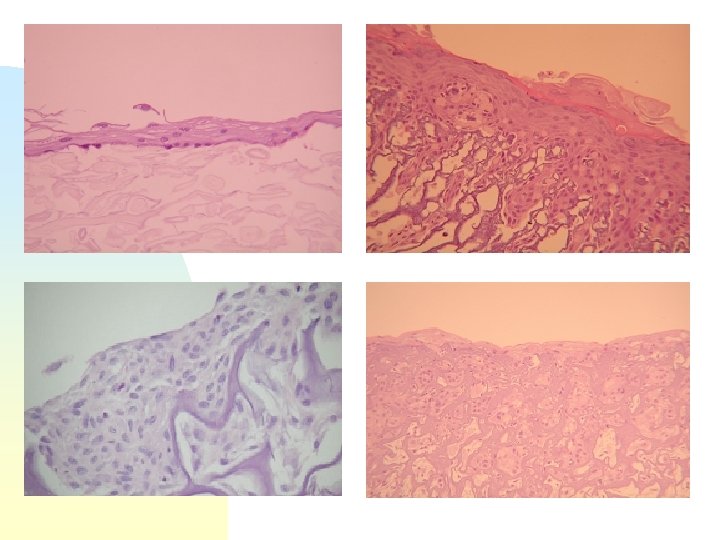

Esame Istologico I limiti del lembo epidermico così ottenuto, che ne riducono la possibilità d’impiego clinico, sono il ridotto spessore e la conseguente fragilità.

Risulta quindi evidente la necessità di impiegare un supporto idoneo da utilizzare come “carrier” per le cellule in coltura.

Ematossilina - eosina 10 x

Ematossilina - eosina 20 x

Ematossilina - eosina 40 x

Strato basale

Strato spinoso

Strato granuloso e corneo

Ematossilina Eosina - 10 x

Ematossilina Eosina - 20 x